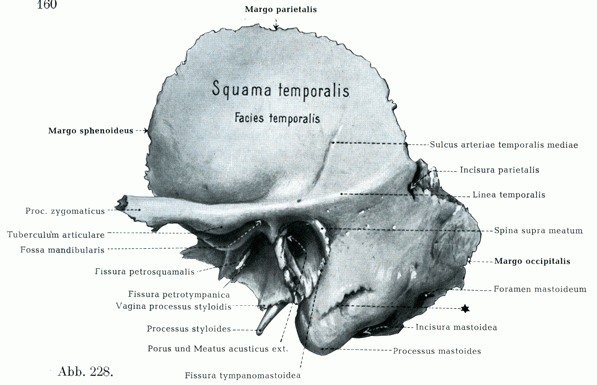

Анатомия и особенности фиссуры петротимпаника